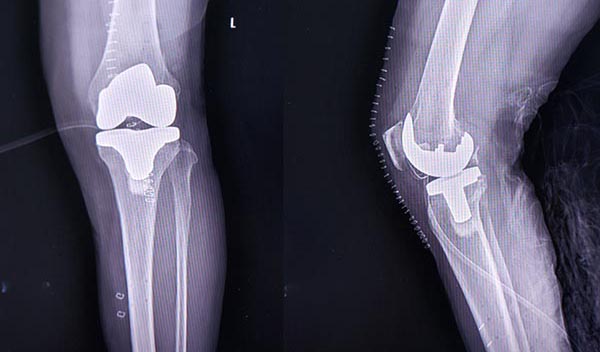

2025年11月5日,海城市正骨医院手术室传来重磅喜讯——副院长兼老年骨伤病及骨关节科主任付伟主任医师率领核心医疗团队,成功为59岁的孙女士实施鞍山地区首例机器人辅助下左侧膝关节置换手术。术中实现毫米级假体定位精度与0度力线误差,标志着鞍山地区膝关节置换手术正式迈入“机器人精准时代”。这是继今年3月份成功实施鞍山地区首例机器人辅助下全髋关节置换手术之后,海城市正骨医院在智慧医疗上的又一重大突破。

今年59岁的孙女士长期被左侧膝关节骨性关节病困扰,近一年来病情持续加重,行走百余米便出现剧烈疼痛,上下楼梯需扶手借力,日常生活深受影响。她于11月3日慕名前往海城市正骨医院老年骨伤病科住院就诊。入院后,付伟团队为孙女士完善了膝关节X线、CT及磁共振成像等全套检查,影像学结果显示其左侧膝关节软骨严重磨损、内侧间隙明显变窄,伴骨赘形成及轻度内翻畸形,符合膝关节置换手术指征。考虑到孙女士希望术后快速康复、恢复高质量生活的需求,医院随即组织多学科专家会诊,最终敲定“机器人辅助下左侧人工全膝关节置换”的手术方案。

11月5日上午9时,手术正式开始。在全身麻醉下,付伟主任医师带领团队先通过光学定位系统完成患者膝关节解剖结构注册,机器人随即生成个性化手术路径。术中,机器人手臂精准执行骨面打磨、假体安放等操作,付伟团队结合30余年关节置换临床经验,实时调整假体平衡度,确保膝关节屈伸功能达到最佳状态。整个手术历时1小时40分钟,手术顺利,患者出血量少,生命体征平稳。